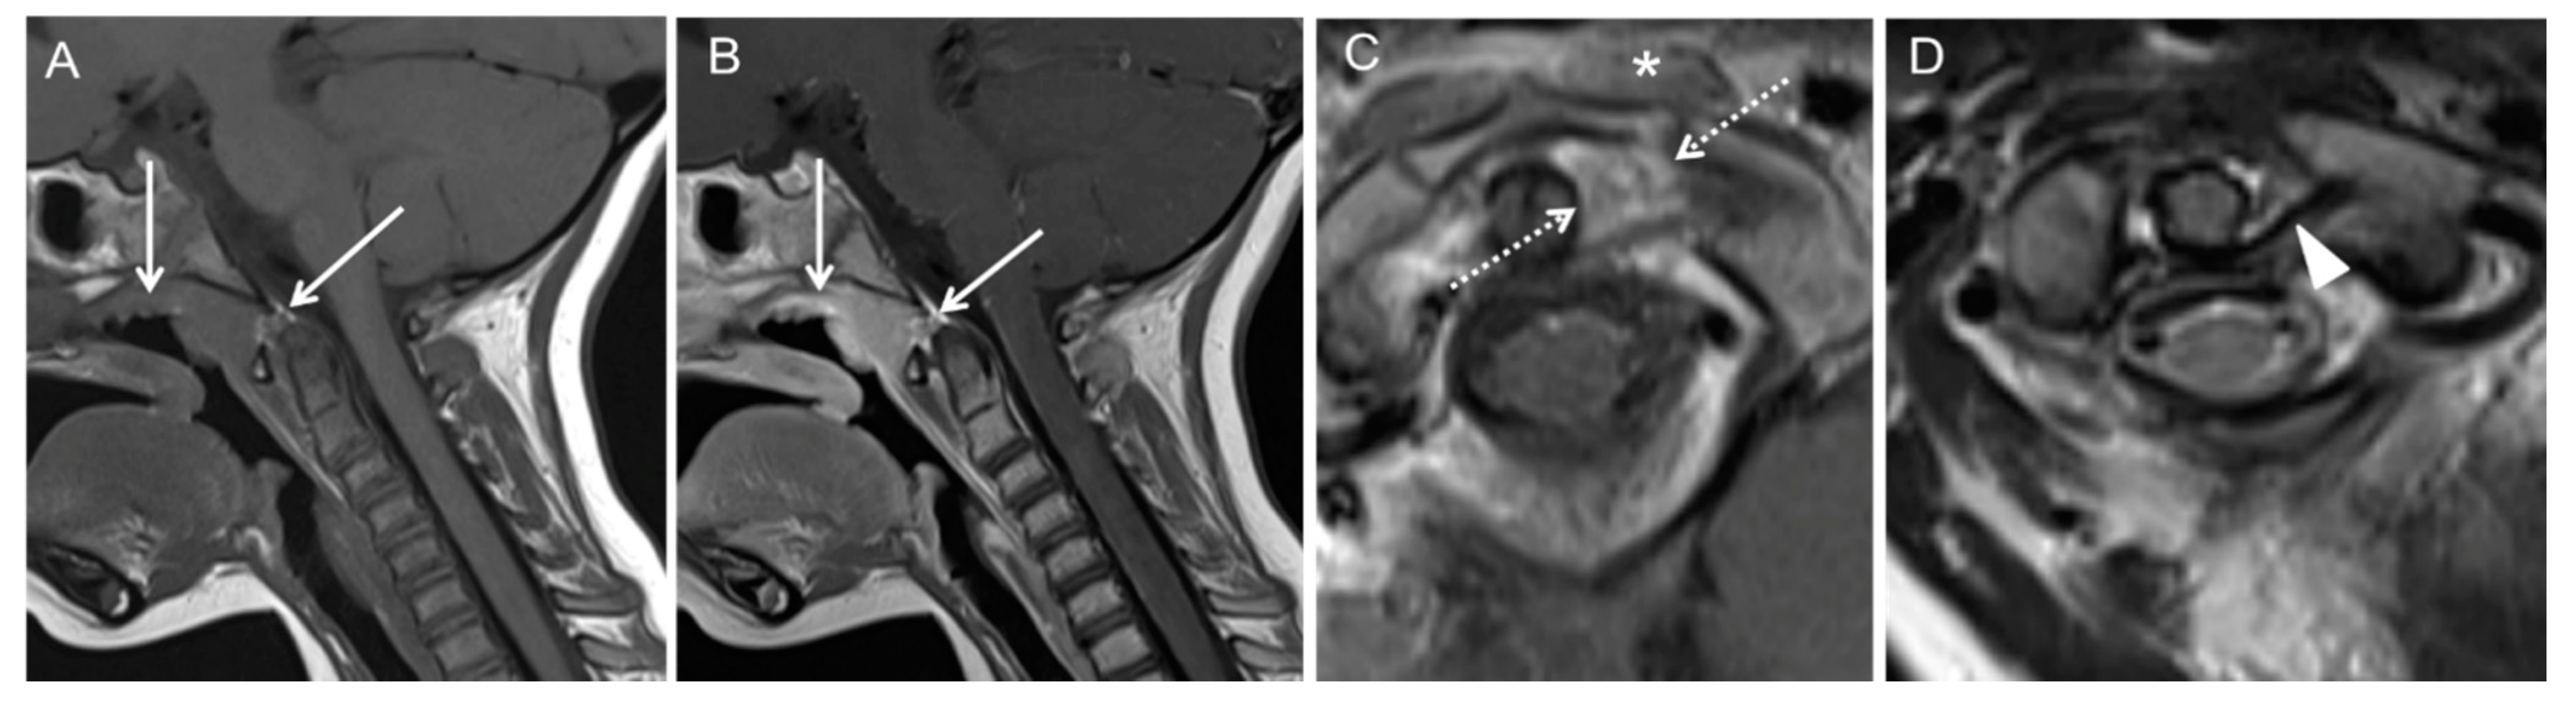

Illustration of Three Pediatric Cases of MRI in Inflammatory Nontraumatic Atlantoaxial Rotatory Subluxation